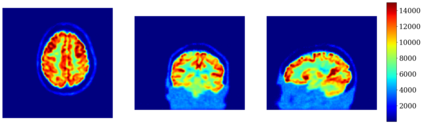

In this work, we investigate hybrid PET reconstruction algorithms based on coupling a model-based variational reconstruction and the application of a separately learnt Deep Neural Network operator (DNN) in an ADMM Plug and Play framework. Following recent results in optimization, fixed point convergence of the scheme can be achieved by enforcing an additional constraint on network parameters during learning. We propose such an ADMM algorithm and show in a realistic [18F]-FDG synthetic brain exam that the proposed scheme indeed lead experimentally to convergence to a meaningful fixed point. When the proposed constraint is not enforced during learning of the DNN, the proposed ADMM algorithm was observed experimentally not to converge.